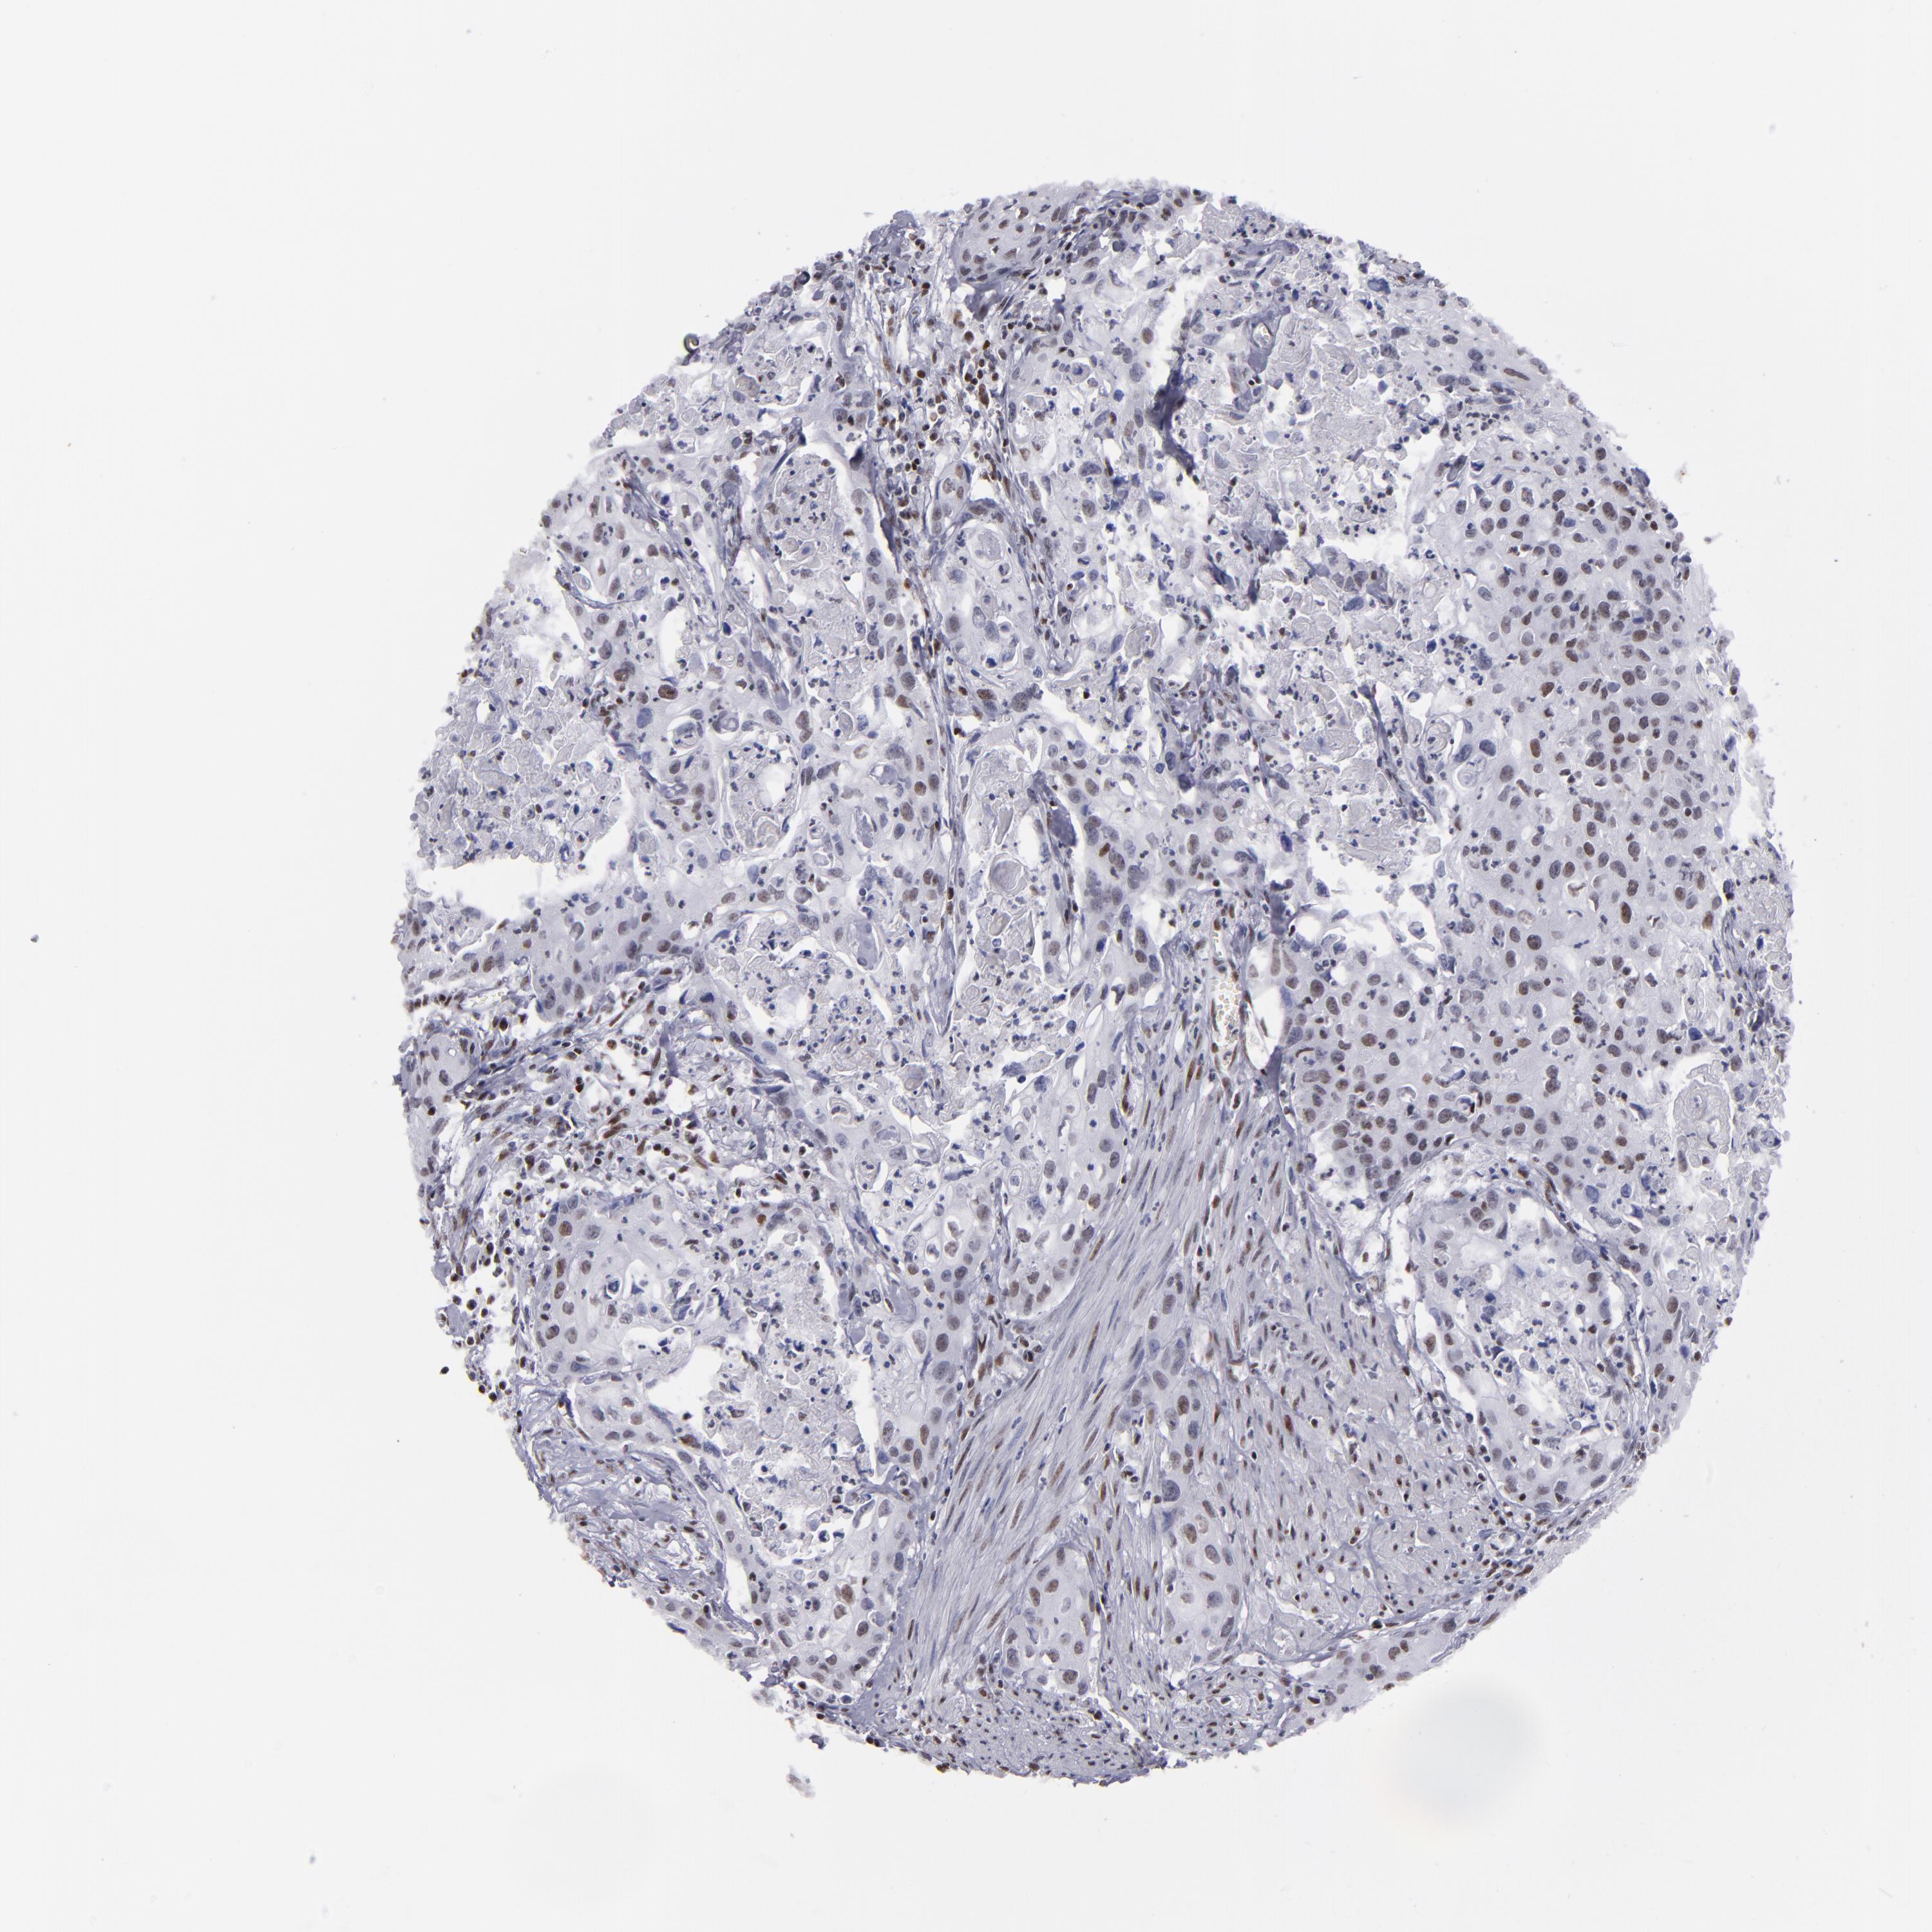

UROTHELIAL CANCER - Protein expressioni

A mouse-over function shows sample information and annotation data. Click on an image to view it in a full screen mode. Samples can be filtered based on level of antibody staining by selecting one or several of the following categories: high, medium, low and not detected. The assay and annotation is described here.

Note that samples used for immunohistochemistry by the Human Protein Atlas do not correspond to samples in the TCGA dataset.

Antibody stainingi

Antibody staining in the annotated cell types in the current human tissue is reported as not detected, low, medium, or high, based on conventional immunohistochemistry profiling in selected tissues. This score is based on the combination of the staining intensity and fraction of stained cells.

Each image is clickable and will lead to virtual microscopy that enables deeper exploration of all samples and also displays staining intensity scores, fraction scores and subcellular localization as well as patient and tissue information for each sample.

Antibody HPA001907

Antibody HPA002735

Antibody CAB010451

Antibody CAB080271

Staining

High

Medium

Low

Not detected

Intensity

Strong

Moderate

Weak

Negative

Quantity

>75%

75%-25%

<25%

None

Location

Nuclear

Cytoplasmic/membranous

Cytoplasmic/membranous,nuclear

Urothelial carcinoma, High grade

Urothelial carcinoma, Low grade

Adenocarcinoma, NOS